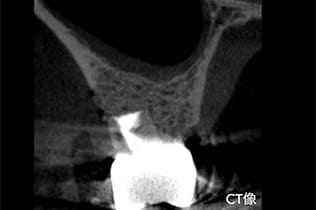

- 診査診断

歯茎の腫れを確認し、CT、レントゲンで確認し、根の先に問題があることを確認します。